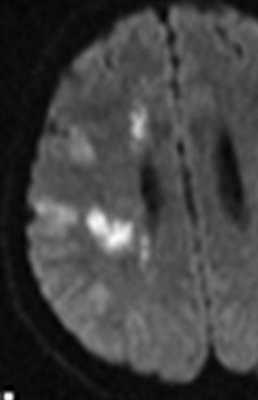

При травме может наблюдаться повреждение сосудов. МРА и КТА могут помочь в выявлении разрывов, расслоений и аневризм. При тяжелой ЧМТ при МРТ может встретиться диффузное аксональное повреждение. Под ним понимают точечные кровоизлияния и очажки непосредственно в белом веществе трактов. Типичны такие очаги на МРТ головного мозга на границе белого и серого вещества, мозолистом теле, стволе мозга. Клиническое течение травмы у таких пациентов более тяжелое и в последствие нередки психические отклонения. взвешенная МРТ. Очаги в мозолистом теле. Очаги могут быть мелкими и плохо видными на обычных МРТ головного мозга.

Субарахноидальное кровоизлияние опасно вазоспазмом, который наблюдается на 5-7 сутки. Сам спазм хорошо определяется при дуплексном сканировании. При МРТ головного мозга можно выявить ранние признаки ишемического инсульта.

МРТ головного мозга. Диффузионно-взвешенная МРТ последовательность. ОНМК в острой стадии вследствие вазоспазма.